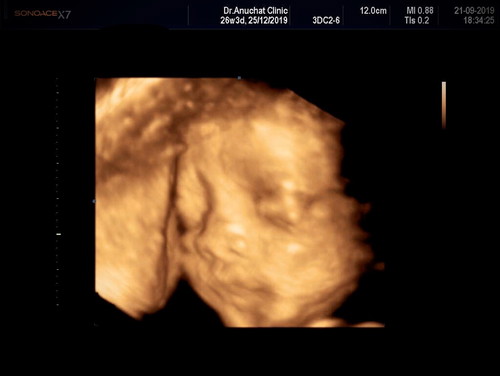

สวัสดีคับแม่ๆผมหนุ่มน้อย26weekคับ ขอดูเพื่อนๆคลอดหน่อยค้าบจะน่าชังขนาดไหนนนน????

น้ององศาจ้า ซาวตอน28วีคจ้า ตอนนี้33วีคแล้วผู้ชาย

ซาวด์ตอน 28W ค่ะ ตอนนี้ 35+5 ผช ค่ะ